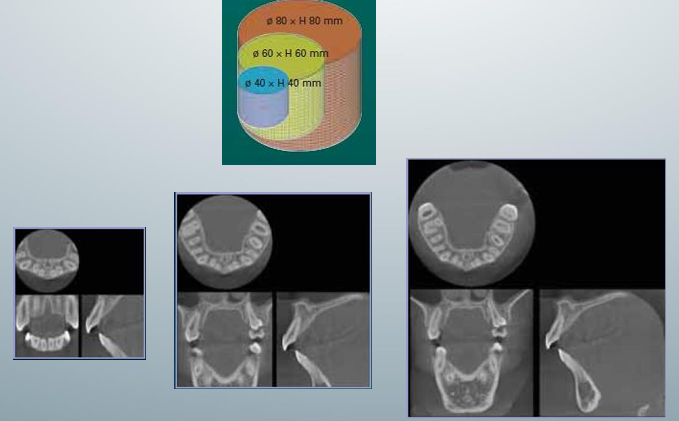

FOV in dentistry

-field-of-view

-anatomical area included in the volume

-consider the balance between dose savings and best image quality

3D exposure, volume example, image for FOV

-top one called “limited”: focused or restricted FOV scans providing high-resolution images of limited regions

-second and third ones “one jaw” or “both jaws”: provide image of the maxilla or mandible or both

-fourth one “face”: images from the skull base to the chin